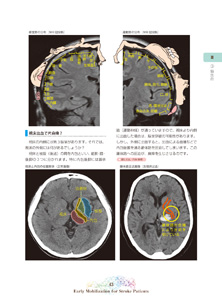

3. 脳出血